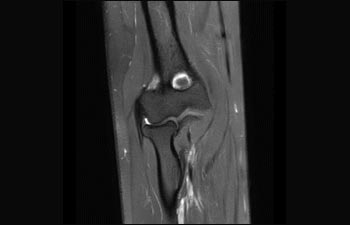

Sehen Sie selbst, was die ersten Nutzer von Ingenia Prodiva 1.5T über ihre Erfahrungen mit dem System und dessen Auswirkung auf ihre radiologische Praxis berichten.

Finden Sie die richtigen klinischen Applikationen für Ihre Anforderungen